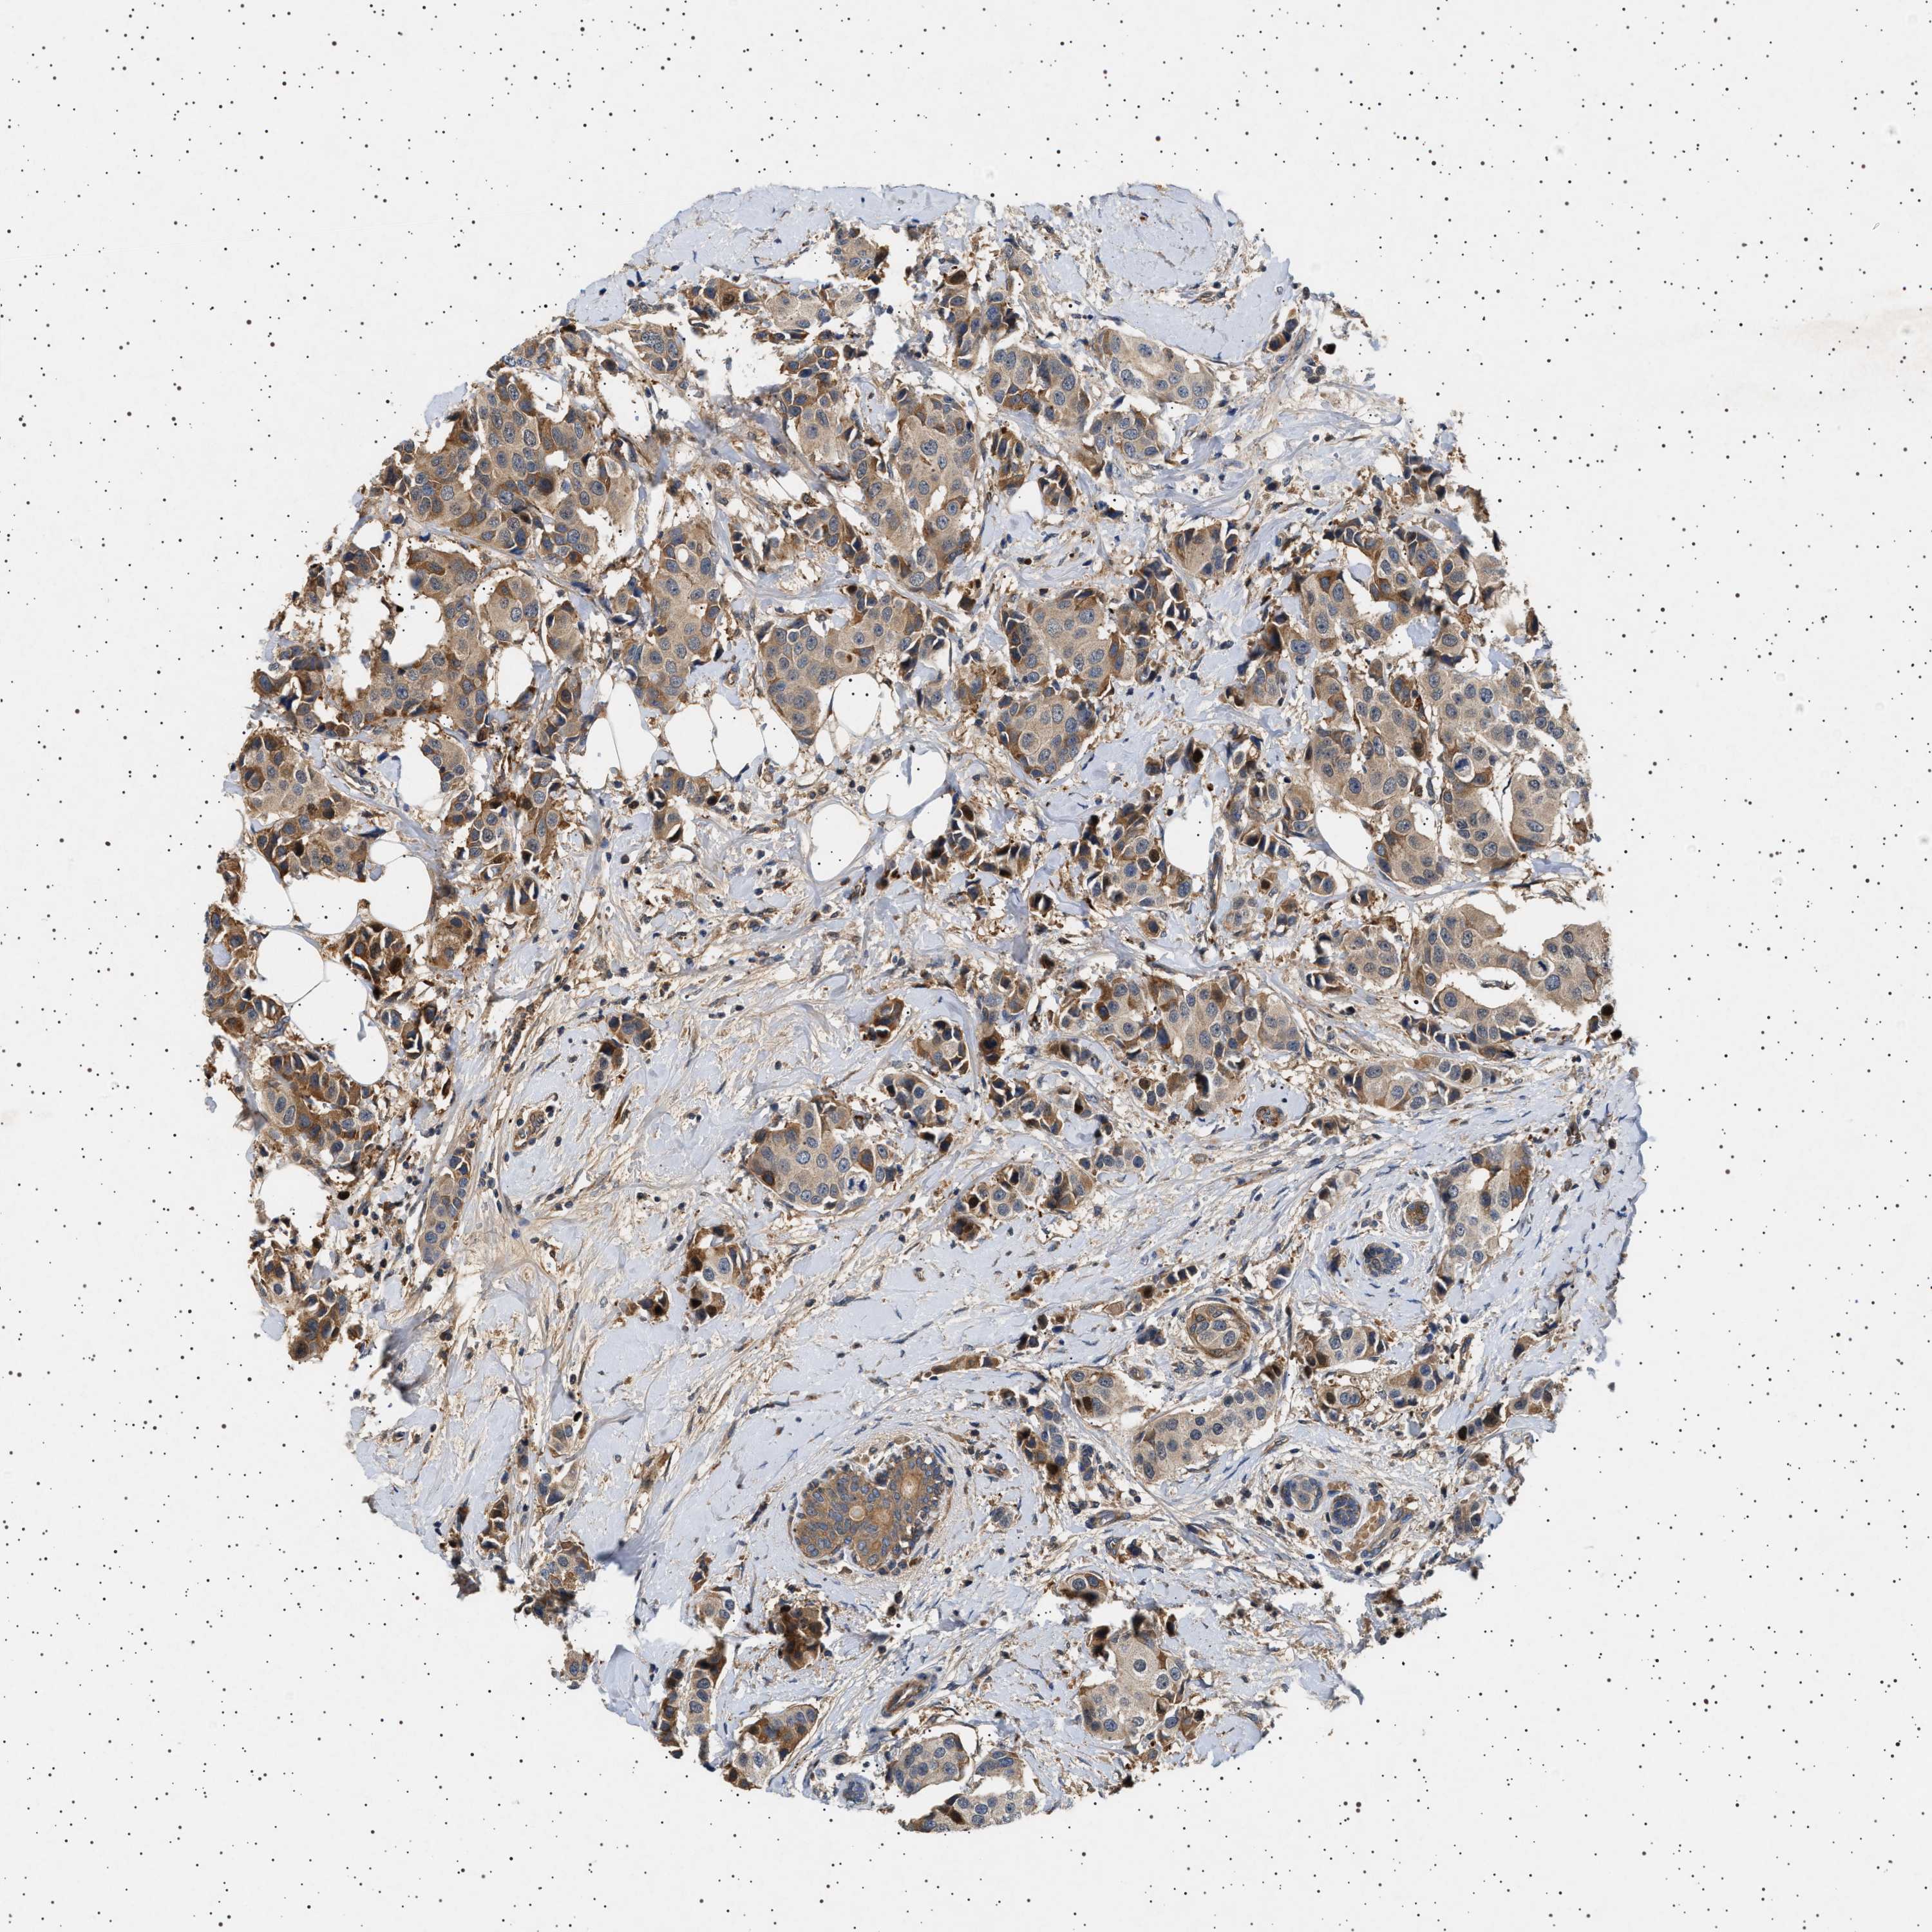

CANCER BREAST CANCER Show tissue menu

BRCA TCGA BRCA VALIDATION PROTEIN EXPRESSION

ANTIBODIES

AND

VALIDATION